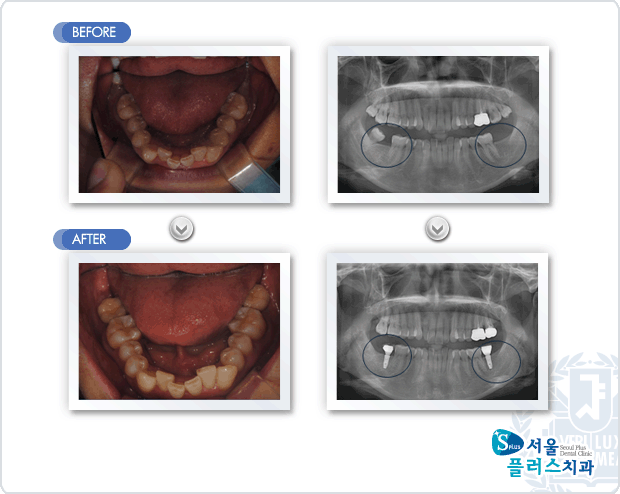

[임플란트] 상악 좌측 제2 대구치의 우식에 의한 통증